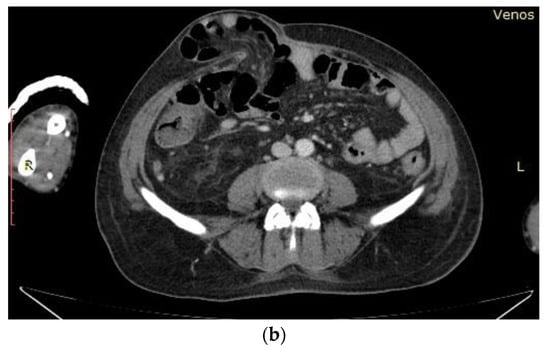

- Pale skin and mucous membranes, jaundice, petechiae on the right forearm, livedo reticularis on the left lower limb, bilateral onycholysis (Figure 1a,b)

- Abdominal distension due to ascites, displaceable dullness on the flanks, non-tender to palpation